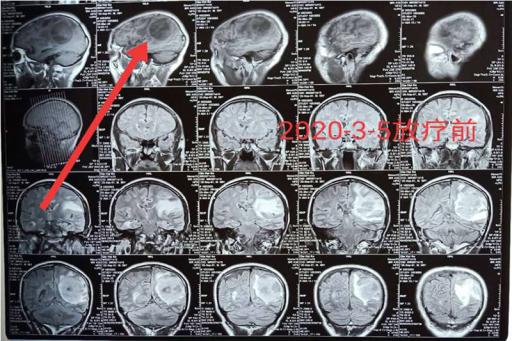

“许大爷肿瘤多发转移了,我们不建议采取手术治疗了,但是,目前大爷头痛明显,针对头部转移灶我们可以使用立体定向放疗—陀螺刀治疗,同时啊,脑袋有多发的转移病灶,我们还需要在此基础上加上全脑放疗,以增加对头部肿瘤的控制效果。”唐三元主任表示。

哪些情况适合开展陀螺刀治疗呢?唐三元主任解释,陀螺刀最适合的就是对于那些肿瘤比较小,个头比较局限,位置又比较深的肿瘤,像许大爷这样的脑转移瘤就非常适合该项技术。其他的还比如,不能去开刀或者是不愿意开刀的肺癌,不能手术的肝癌等等都可以根据情况开展局部放疗也就是陀螺刀治疗。当然,对于那些空腔脏器上的肿瘤如食道癌、胃癌、肠癌还是不能行该项技术的。肿瘤太多的话,像这位许大爷,我们就在陀螺刀的基础上还加上了全脑放疗,因此,才取得了这么好的效果!